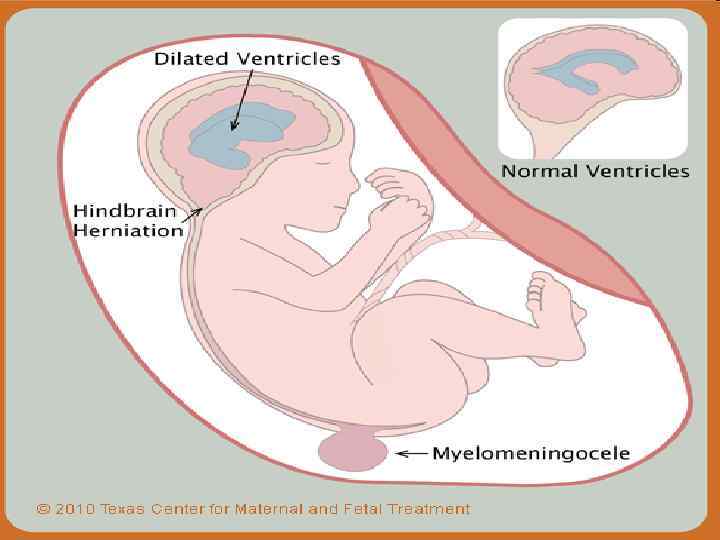

SPINA BIFIDA 111

Менингорадикулоцеле 112

Менингомиелоцеле 113

114

115

Ребенок со spina bifida 116

117

118

119

120

121

122

123

124

125

126